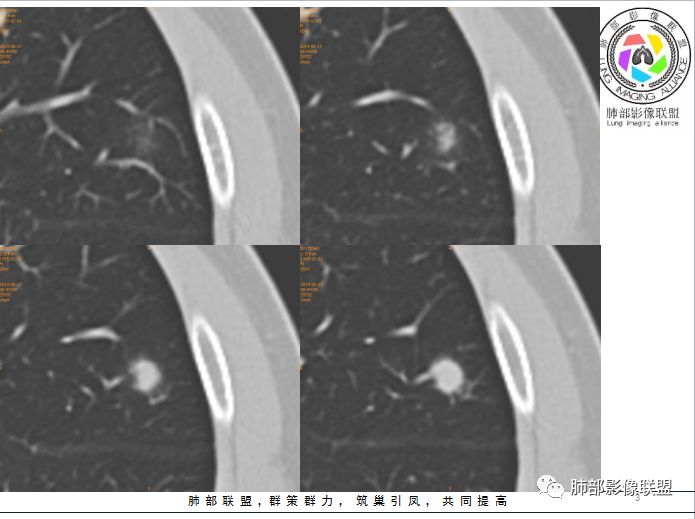

孤立结节型隐球菌影像表现:

划重点:1、胸膜下、两下肺多见。

2、“3个1/3”:1/3与胸膜相连,1/3内部可见空泡征,1/3有晕征

3、“2个2/3”:2/3与胸膜有间隙,2/3近段与血管相连。

1、与炎性假瘤、恶性肿瘤鉴别:恶性肿瘤边缘膨隆,收缩也是毛毛糙糙的,炎性假瘤收缩力较强,边缘凹陷的多。隐球菌孤立结节收缩力弱,膨胀力也弱,与胸膜关系多为糊墙,部分有间隙。右边两幅可以看到胸膜增厚,胸膜下脂肪间隙增宽。晕中长毛刺,边缘平直,血管走行自然,鉴别肺癌。